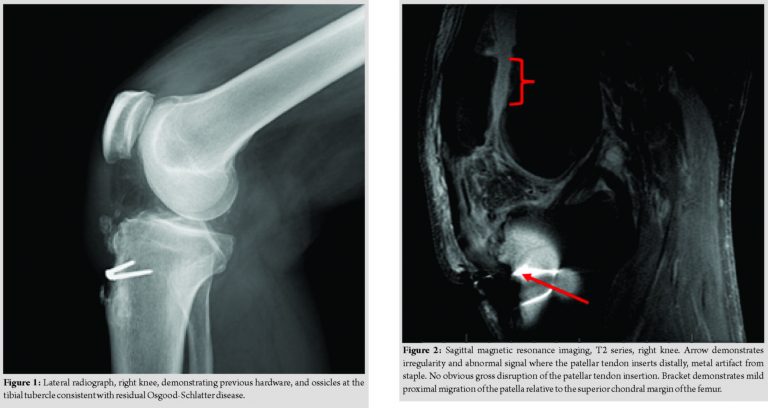

Radiographs revealed a staple from his prior procedure. On the lateral view, several exostoses remained apparent at the tibial tubercle. There was a mild superior migration of the patella compared to a contralateral knee image (Fig. 1). Because of the patient’s history, atypical findings on physical examination, and radiographs; a magnetic resonance imaging (MRI) was performed, revealing a tear of the medial aspect of the distal patellar tendon near the insertion on the tibial tubercle and metallic staple. The examination was limited due to artifact from the staple. MRI demonstrated a normal-appearing patellar tendon inserting onto the inferior pole of the patella (Fig. 2). Given the combination of an MRI confirming a compromised patella tendon and a clinical exam of tenderness over the insertion on the tibial tubercle, lack of ability to perform a straight leg raise and an extension lag; surgical intervention was determined necessary. A knee arthroscopy, examination under anesthesia, and open patellar tendon reconstruction were planned.